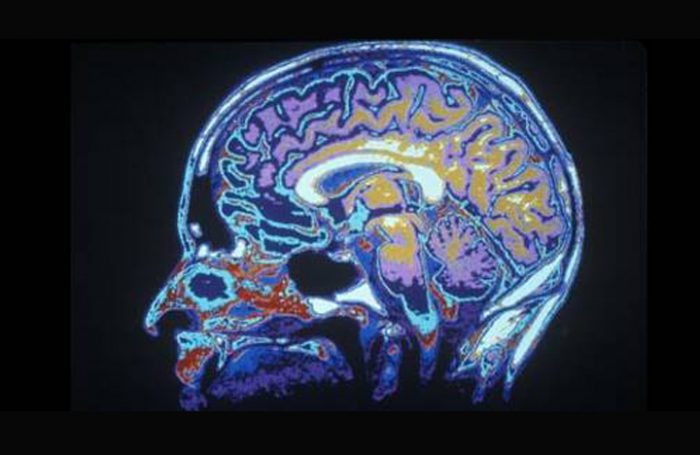

El Nobel de Medicina 2014 premió a un científico estadounidense y a dos noruegos por revelar el «GPS interno» del cerebro, las células que constituyen el sistema de posicionamiento que hace posible la orientación en el espacio.

Los hallazgos del estadounidense John O’Keefe y el matrimonio formado por May-Britt y Edvard I. Moser han supuesto un cambio en el paradigma de la comprensión de funciones cognitivas superiores y abierto nuevas vías para entender el funcionamiento de la memoria, el pensamiento o cómo hacer planes, señala el Instituto Karolinska.

Recientes investigaciones han mostrado que esas células existen también en seres humanos, por lo que el conocimiento del sistema de posicionamiento cerebral podría ayudar a entender la pérdida de memoria espacial de los enfermos de Alzheimer, añade en su fallo esa institución con sede en Estocolmo, que otorga cada año el galardón.

Usando métodos neuropsicológicos O’Keefe descubrió en 1971 que cuando una rata se encontraba en un lugar determinado de una sala, siempre se activaba un tipo de célula en el hipocampo, una de las principales áreas del cerebro humano y de otros mamíferos.

Esas células no sólo registraban un impulso visual, sino que construían un mapa interno del medio, por lo que concluyó que el hipocampo genera múltiples mapas representados por la actividad colectiva de las células activadas en diferentes lugares.

Tres décadas después, mientras trabajaba con las conexiones en el hipocampo de las ratas, el matrimonio Moser descubrió en la corteza entorrinal, un área cerebral vecina, otras células que se activaban cuando los individuos pasaban localizaciones múltiples dispuestas en una red hexagonal.

Cada célula se activaba en un modelo espacial único y en conjunto formaban un sistema de coordenadas que permitía la navegación, a la vez que creaban circuitos con las células del hipocampo, constituyendo ese «GPS interno» del cerebro.